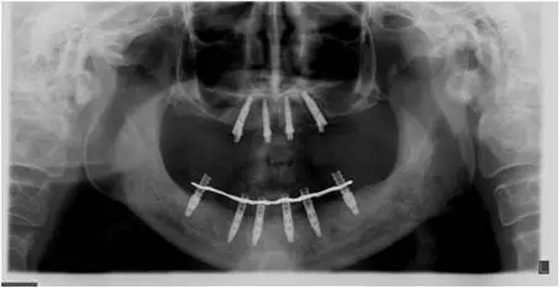

患者男性,51歲,全口無(wú)牙,下頜骨量尚可,上頜后牙區(qū)上頜竇底剩余骨高度嚴(yán)重不足,前牙區(qū)牙槽突較豐滿,主訴希望全口種植固定義齒修復(fù)。于2015年 9月接受種植治療:上頜采用All-on-4種植方案、下頜采用常規(guī)種植6顆種植體方案,種植后行即刻修復(fù)(圖1-2)。

10個(gè)月后出現(xiàn)左上頜咬合痛,X線檢查發(fā)現(xiàn)上頜左側(cè)前磨牙區(qū)傾斜種植體周圍低密度影,臨床檢查種植體松動(dòng),其余種植體骨結(jié)合良好,遂拔除該種植體(圖3-4)。愈合3個(gè)月,CBCT片顯示:25區(qū)種植窩空虛(圖5),愈合不佳,26區(qū)竇底剩余骨高度不足2mm(圖6),其余種植體骨愈合良好,15區(qū)傾斜種植體邊緣骨疑似吸收至第三螺紋(結(jié)合全景片)?;颊咭蠊潭ㄐ迯?fù)。

2、增加上頜種植體數(shù)量,分別與16、25、26植入3顆,行6顆種植體支撐的常規(guī)種植固定義齒修復(fù)(圖7)。16、25、26區(qū)剩余骨高度嚴(yán)重不足是該方案的不利方面,存在因需要上頜竇底提升手術(shù)所帶來(lái)的相應(yīng)手術(shù)風(fēng)險(xiǎn)。但是,上頜竇底提升術(shù)是一個(gè)成熟、可靠的技術(shù)方法,經(jīng)過(guò)與患者充分溝通,最終選擇了這一方案。

2、6個(gè)月后延期種植,分別與16、25、26植入3顆種植體(如圖7所示);